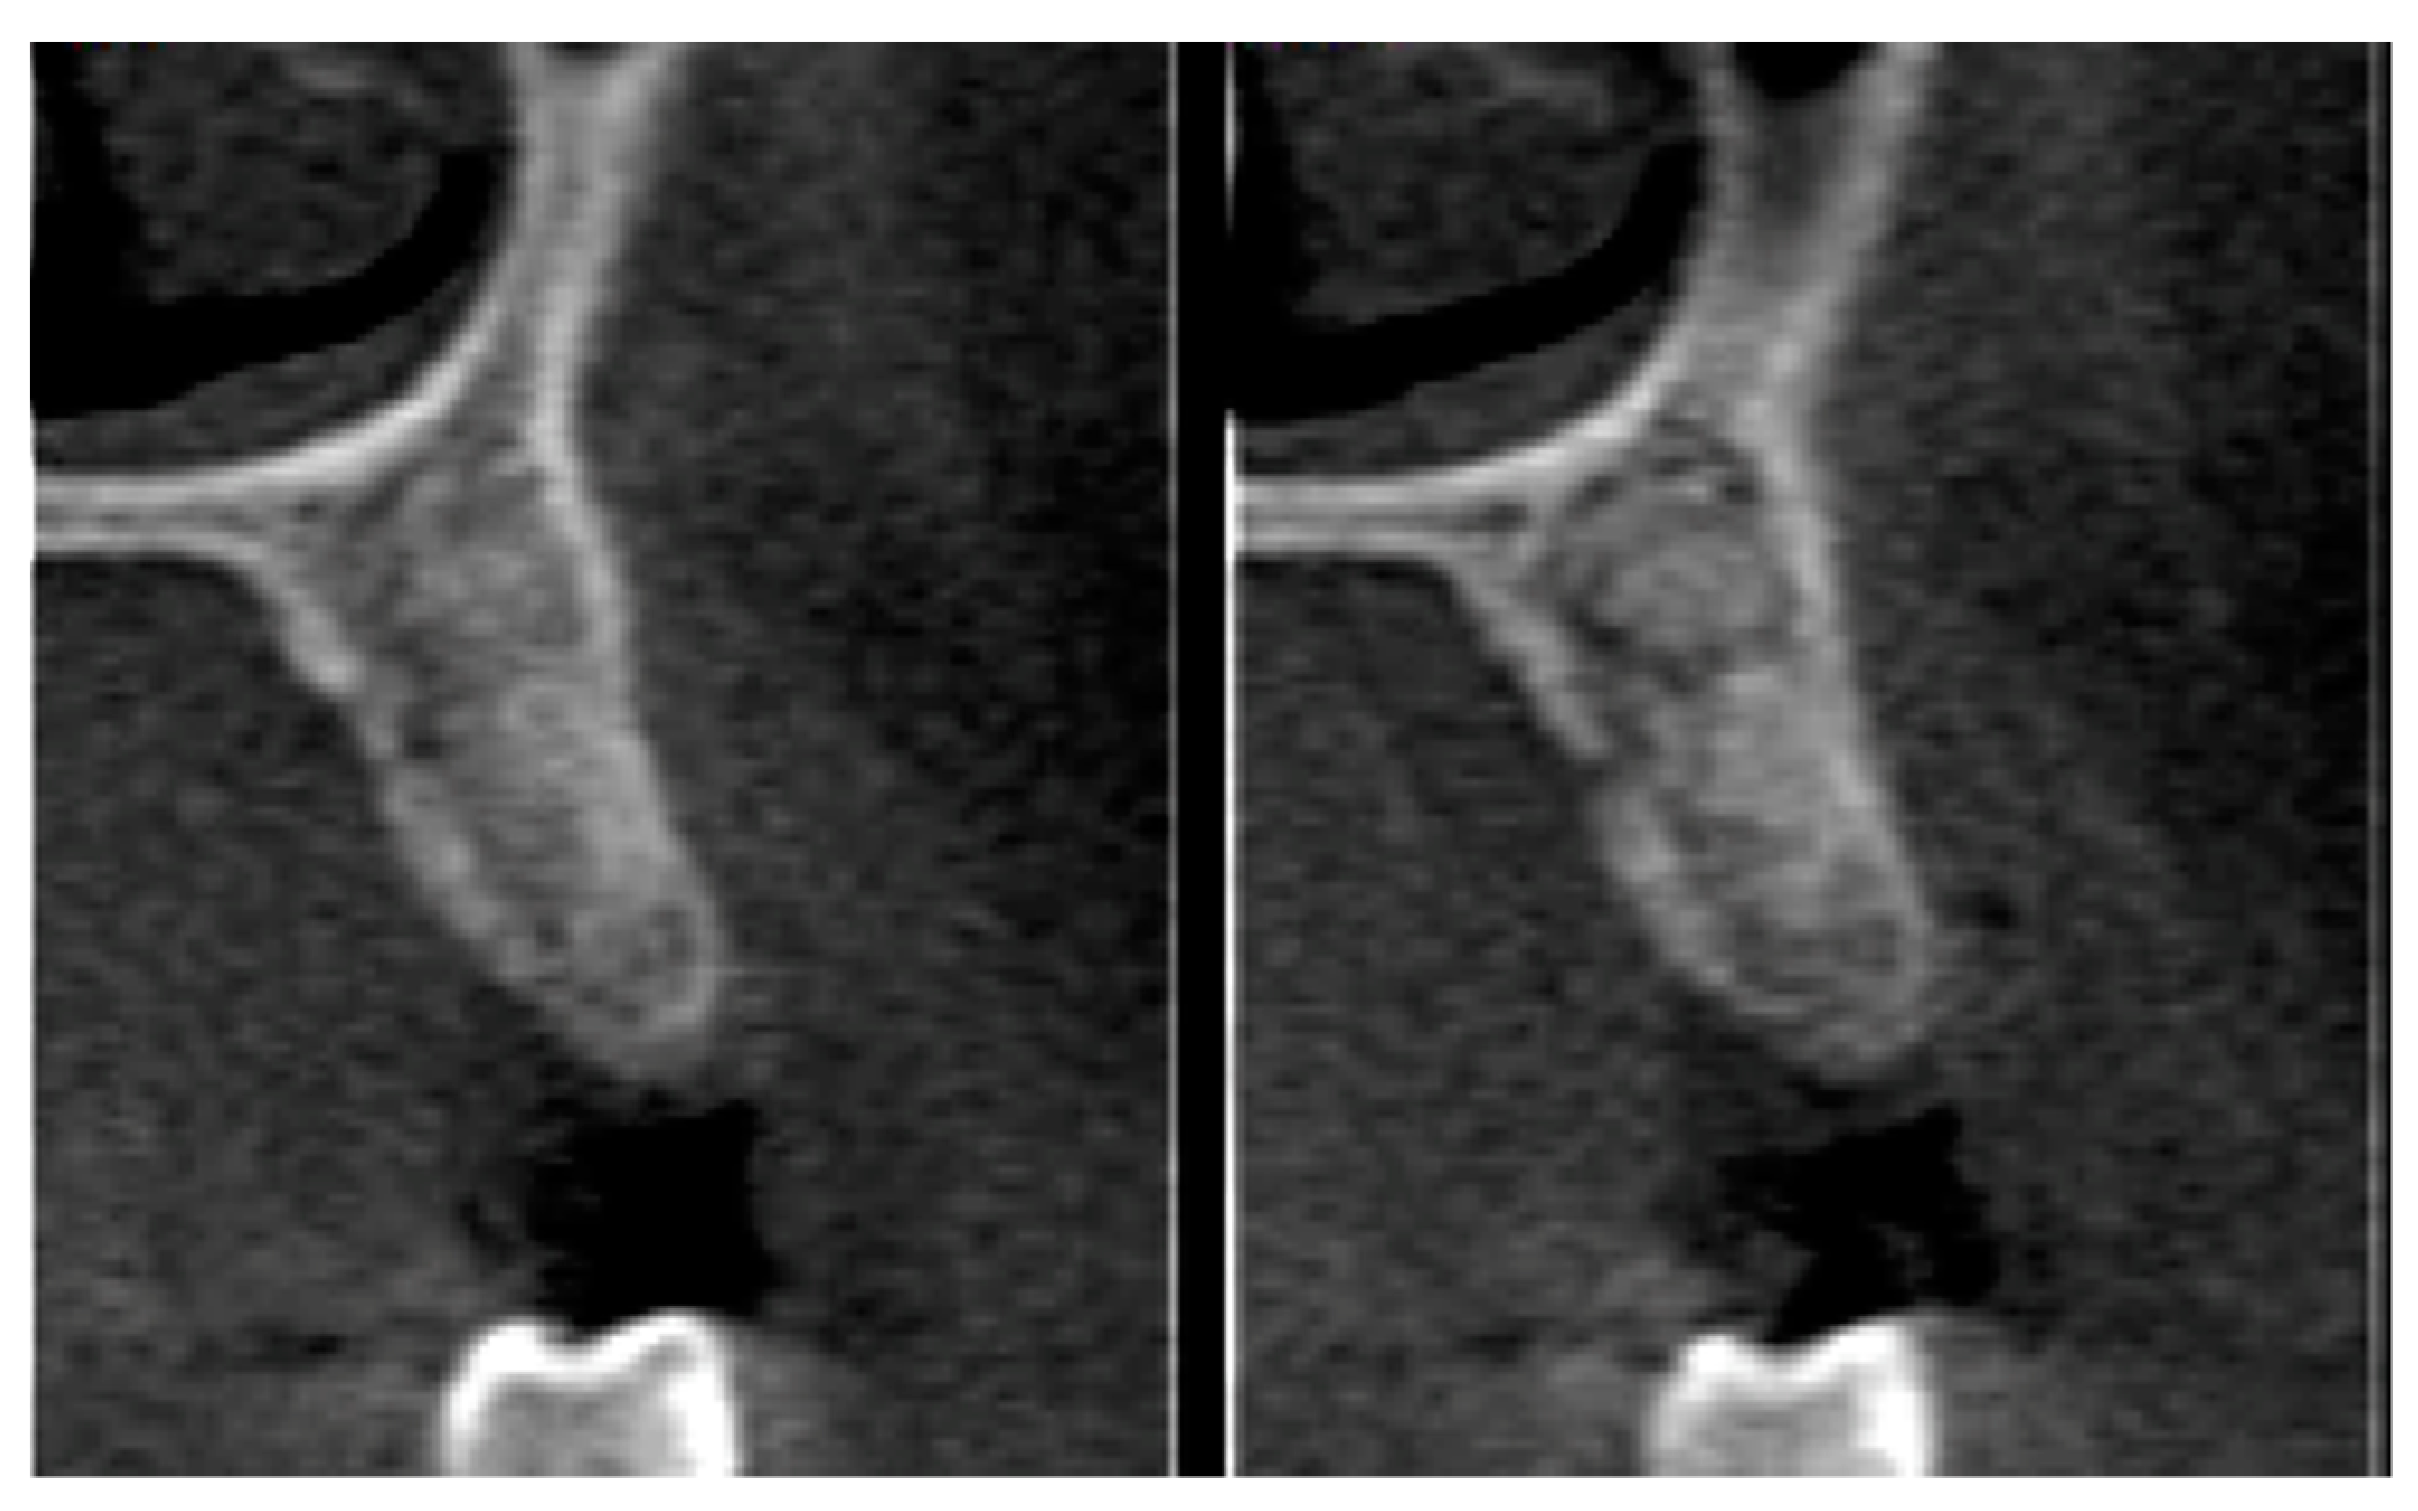

2.6. Tomographic Analysis